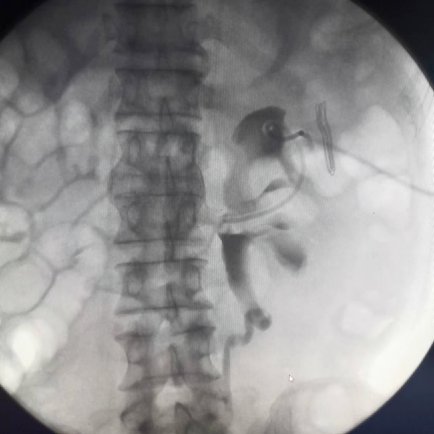

ERCP

造影顯示效果,借助內(nèi)窺鏡進行ERCP操作,是一種微創(chuàng)的肝內(nèi)膽管取石的治療方式。

是膽道術(shù)后T管引流患者的常規(guī)檢查方法,可以了解術(shù)后膽道內(nèi)有無殘留結(jié)石、膽道狹窄及Oddi括約肌的暢通情況。